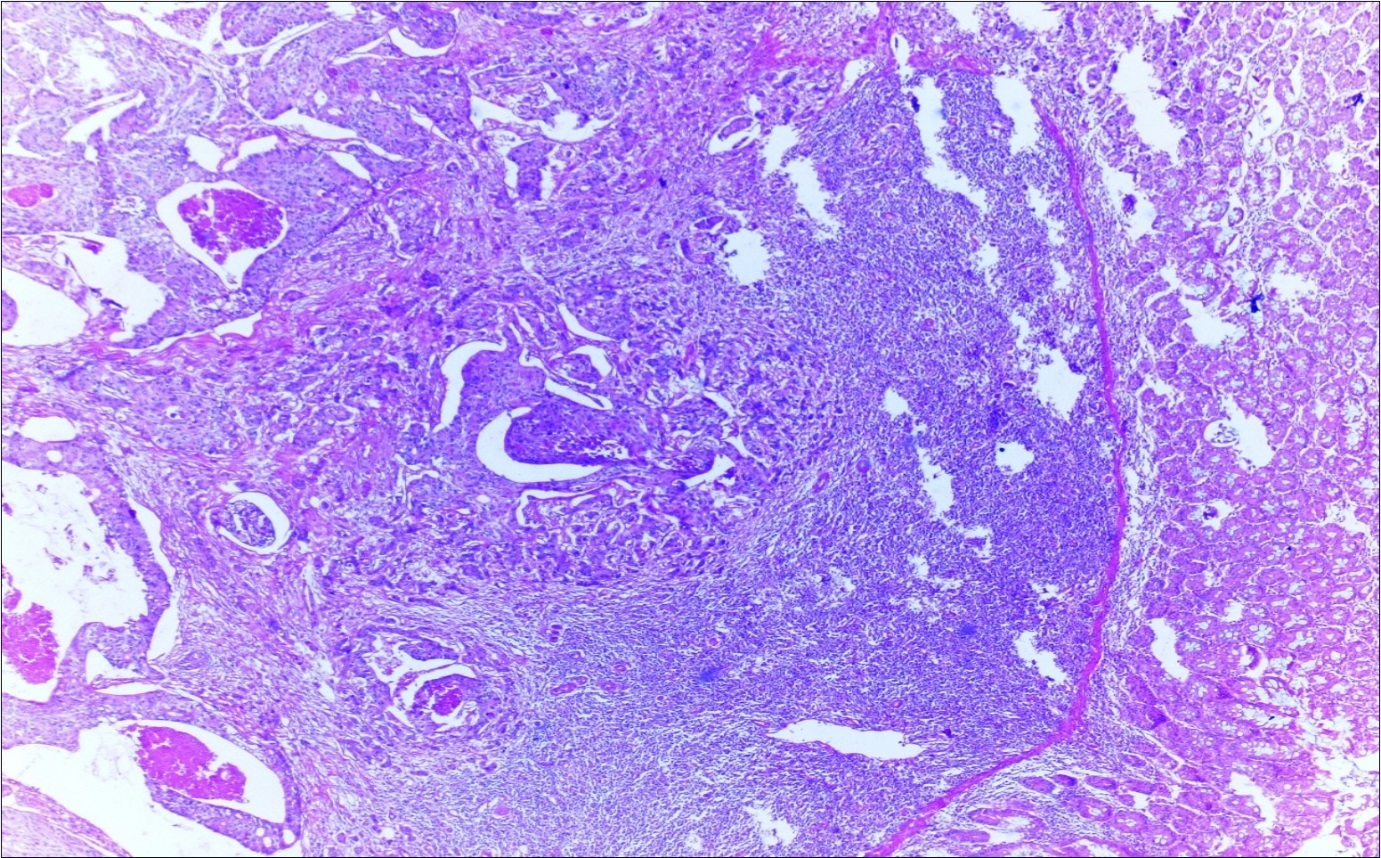

A 63-year-old woman presented to the Department of General Surgery as an outpatient with abdominal pain. Physical examination showed the signs of acute appendicitis and appendectomy was performed. During microscopic examination, a small focus of atypical monotonous lymphoid cell population was seen and the material was sampled totally. The pathological examination revealed MALT lymphoma (Figure 1), with diffuse positivity of cluster of differentiation (CD) 20 (Figure 2), CD 79a and B-cell lymphoma (Bcl- 2) (Figure 3) with just a few CD3 positive lymphoid cells. However, no evidence of adenocarcinoma was found in the appendectomy specimen. After the diagnosis of lymphoma, a complete colonoscopy was planned and this revealed a solid tumoral mass in the caecum measuring 5x4x4 cm. Computed tomography of the abdomen and pelvis revealed mesenteric lymphadenopathy associated with a mass in the caecum with multiple nodules in liver consistent with metastasis (Figure 4). Frozen sections were not obtained since the treatment method would not be affected. The patient underwent anterior resection with regional lymphadenectomy, with the pathological assessment of the resected specimen revealing a collision tumor consisting of a poorly differentiated adenocarcinoma extending through the muscularis propria with MALT lymphoma (Figure 5). Microscopic evaluation of the 11 regional lymph nodes in the mesentery of the resected colon and liver biopsy showed diffuse infiltration of MALT lymphoma with metastasis of adenocarcinoma (Figure 6). According to immunohistochemistry, atypical lymphocytes were positive for CD 20, Bcl-2, and negative for CD3, CD5, CD10, CD23, Bcl-6, terminal deoxynucleotidyl transferase, and cyclin D1. The proliferation fraction (MIB-1 immunostaining) was approximately 20%. The morphological and immunohistochemical findings were used to confirm the diagnosis of synchronous presentation of MALT lymphoma and colon adenocarcinoma within the caecum, mesenteric lymph nodes and liver metastases.

Figure 6.Adenocarcinoma with MALT lymphoma infiltration of lymph node (h&e;200)